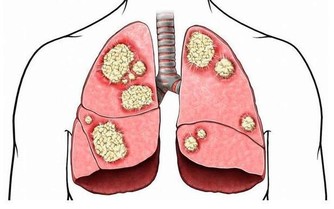

雖然科學還不能提供人類大腦結構變化的確切證據,但按照他的假設,大腦的功能在過去20年間的改變,很可能比過去數千年的變化更大。數字技術對於大腦進化的意義,可以與30萬年前人類祖先第一次學會使用工具相提並論—— 工具的使用導致了大腦額葉與前額葉皮層區的急劇變化,從而促進了語言與社交功能的進化。